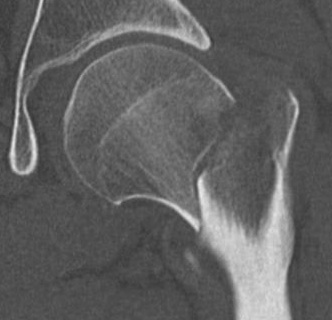

Pauwel's Classification

Based on vertical orientation of fracture line

- increased verticality / increased shear

- increased risk of noonunion / AVN

Type I: < 30° from horizontal

Type II: 30 - 50° from horizontal

Type III: > 50° from horizontal

Pauwel's type III